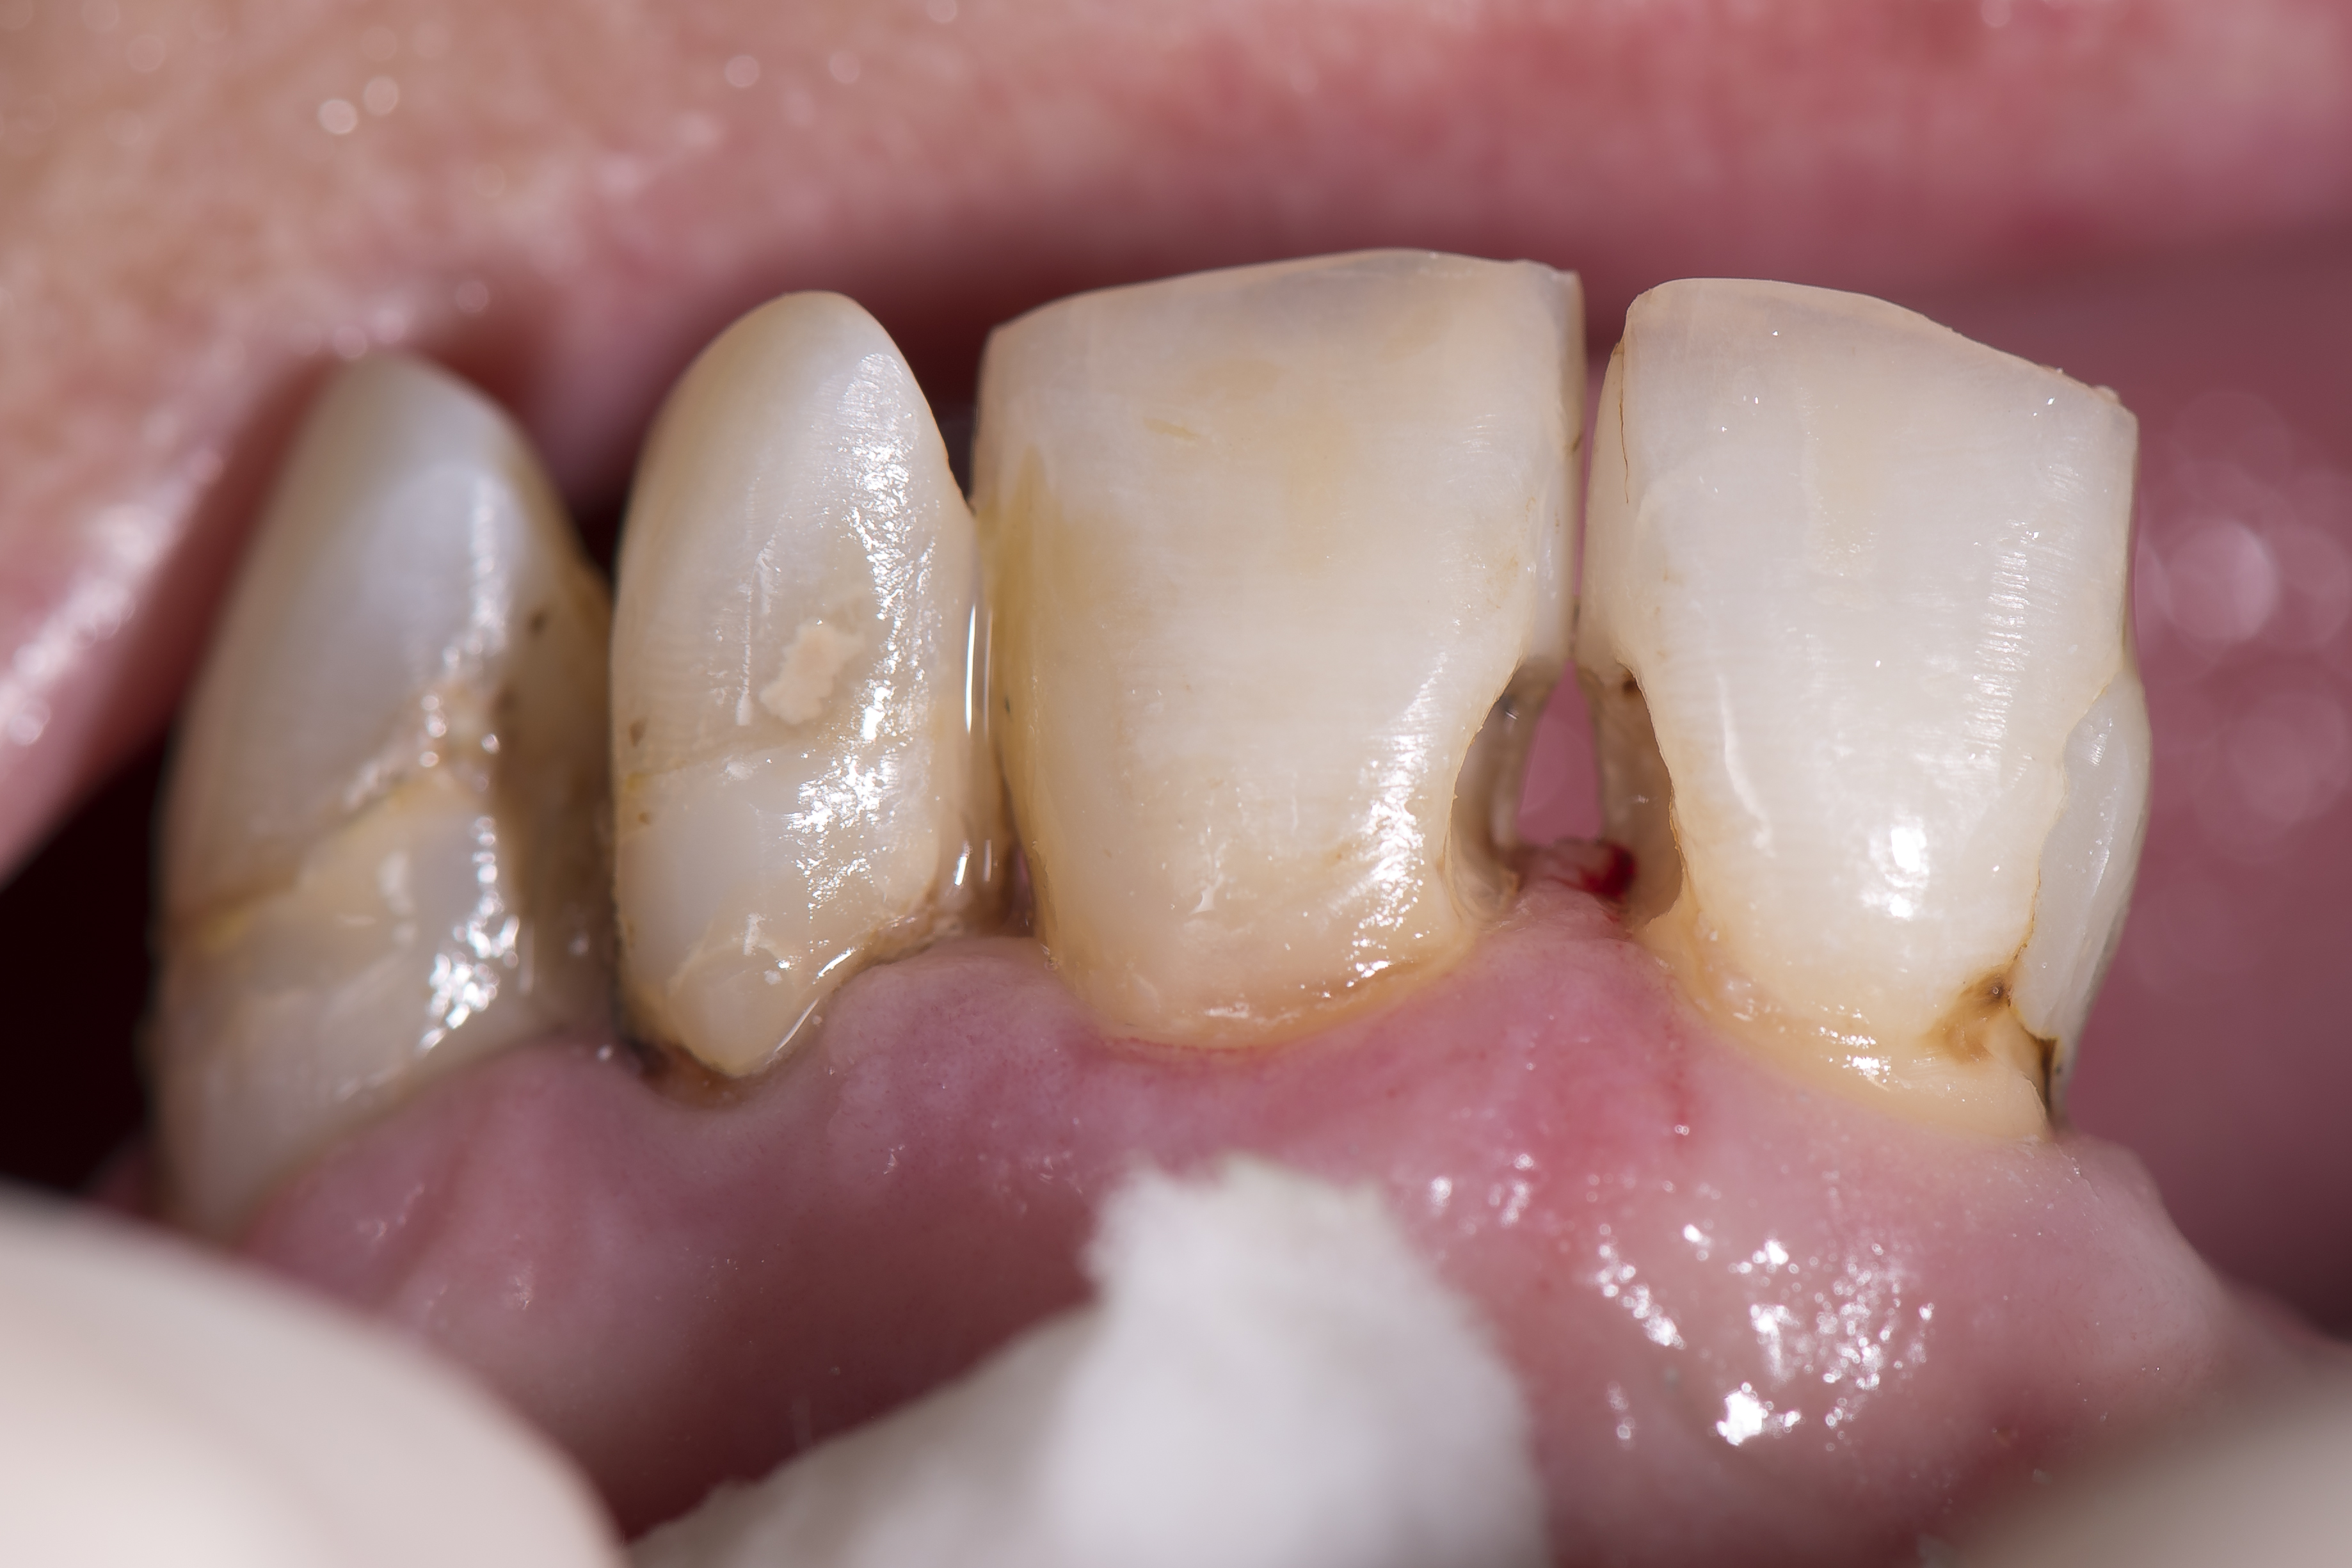

Ryc. 5. Ubytki były stopniowo opracowywane i wypełniane na kolejnych wizytach.

W ciągu kilku kolejnych wizyt przeprowadzono leczenie zachowawcze w obrębie zębów, związane z preparacją kolejnych ubytków próchnicowych i ich wypełnianiem. Objęło ono: ubytek klasy III M i D w zębie 11, ubytek klasy III M i D w zębie 21, ubytek klasy III M i V w zębie 22, oraz ubytek klasy V okrężny w zębie 23. Zastosowano materiał kompozytowy OptiShade (Kerr) w odcieniu MEDIUM w przypadku wszystkich wypełnień. Procedura kliniczna w każdym przypadku wyglądała tak samo (ryc. 6).

Ząb był izolowany przy pomocy koferdamu OptiDam (Kerr) i dokonano preparacji ubytku próchnicy pierwotnej lub też usunięto nieszczelne wypełnienie kompozytowe – w przypadku zębów 22 i 23 były to wypełnienia klasy V, pod którymi zaczęła rozwijać się próchnica okrężna obejmująca powierzchnię korony zęba i korzenia (ryc. 7).